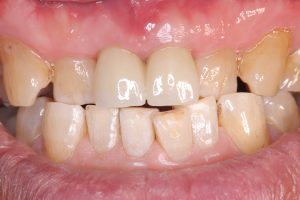

朝からインプラントセット

暮れにオペ抜歯即時、2ヶ月でセット

次は数年前他院で根切したが、また再発し口蓋が腫れてる

被せ物は6本ジルコニア連結